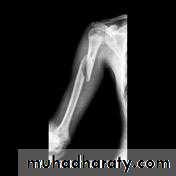

Intercondylar fracture of humerus:

Failure to diagnose these injuries can lead to significant long term disability. Fortunately as these injuries involve an apophysis rather than an epiphysis, no growth arrest of the arm occurs, however elbow instability and even recurrent dislocations can result from suboptimal healing.Fifty percent of medial epicondyle fractures are associated with an elbow dislocation.

It is important to distinguish a medial epicondyle fracture (common) from a medial condyle fracture (very rare). Medial condyle fractures are intraarticular, extending into the elbow joint and require urgent open reduction internal fixation (ORIF).